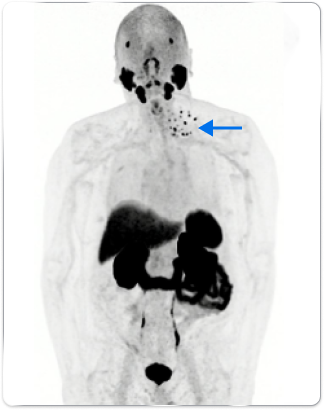

Patient B

Anterior whole body PYLARIFY PET MIP showed uptake in multiple left lower-cervical and supraclavicular lymph nodes (blue arrow)

In patients with similar profiles, PYLARIFY identified differences in extent of disease, guiding treatment changes

- Treatment with IMRT to lymph nodes + ADT

- Post-radiation PSA levels dropped to 0.04 ng/mL